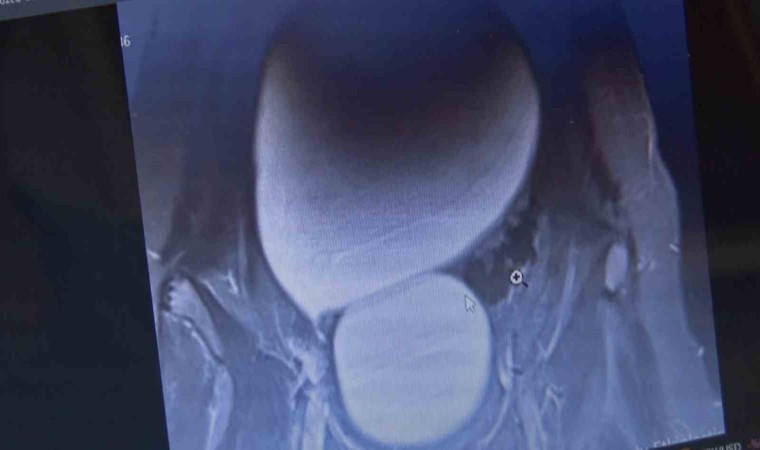

Sivas’ta yaşayan 12 yaşındaki N.B. şiddetli karın ağrıları ve düzensiz adet kanamaları şikayetiyle hastaneye başvurdu. Yapılan detaylı tetkikler sonucunda genç kızın karın bölgesinde yaklaşık 25 santimetre çapında adeta kavun büyüklüğünde bir kist olduğu tespit edildi. Medicana Sivas Hastanesi’nde Çocuk Cerrahisi Uzmanı Op. Dr. Mahmut Aluç tarafından gerçekleştirilen başarılı bir operasyonla, genç kızın sol yumurtalığında bulunan ve karaciğere kadar uzanan devasa kist içerisindeki 1.6 litre su boşaltılıp, başarıyla çıkarıldı. Sağlığına kavuşan genç kız taburcu edildi.

Çocuk Cerrahisi Uzmanı Op. Dr. Mahmut Aluç, kisttin içerisinden yaklaşık 1.6 litre sıvı boşaltıldığını söyleyerek, “ Karın ağrısı, düzensiz adet şikayetiyle bize geldi. Dışarıda yapan tetkiklerde ve bizde yapılan tetkiklerinde karın içerisinde yaklaşık yirmi beş santimetrelik çapında bir kitli kitle tespit ettik. Burada da tetkiklerimize tekrar baktığımızda sol över kökenli bir kisttik yapı olduğunun farkına vardık. Gerekli incelemeleri yaptıktan sonra ve ailenin onayını aldıktan sonra hastayı operasyona aldık. Karaciğere kadar uzanan bir kisttik yapımız vardı. Onun içerisinde yaklaşık 1.6 litre sıvı boşalttık. Over dokusunu, yumurtalık dokusunu koruyarak kisti tamamen eksize ettik. Hastamızı şifayla taburcu ettik. Patoloji sonucumuz da iyi huylu olarak geldi” dedi.